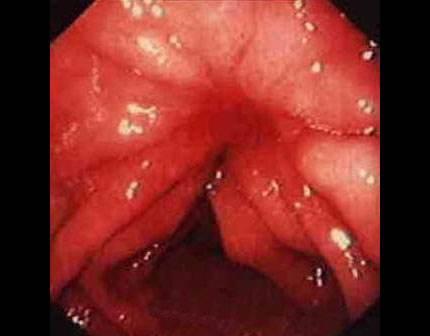

痔瘡癌變的10個(gè)前兆

1、痔瘡疼痛加?。褐摊徎颊呷绺杏X疼痛逐漸加劇,可能是癌變的一個(gè)信號。

2、痔瘡出血:長期痔瘡出血,尤其是出現(xiàn)持續(xù)性出血時(shí),應(yīng)警惕癌變的可能。

3、痔瘡體積變化:如痔瘡體積在短時(shí)間內(nèi)迅速增大,可能是癌變的征兆。

4、排便習(xí)慣改變:如排便頻率增加或減少,以及出現(xiàn)便秘與腹瀉交替的情況,可能與痔瘡癌變有關(guān)。

5、肛門不適:出現(xiàn)肛門墜脹、異物感等癥狀時(shí),應(yīng)考慮痔瘡癌變的可能性。

6、消瘦和乏力:如體重迅速下降、乏力等全身癥狀出現(xiàn)時(shí),可能是痔瘡癌變的警示信號。

7、淋巴結(jié)腫大:如出現(xiàn)腹股溝或盆腔淋巴結(jié)腫大,可能與痔瘡癌變有關(guān)。

8、食欲減退:長期食欲減退,尤其是伴有上述癥狀時(shí),應(yīng)警惕痔瘡癌變。

9、肛周瘙癢:肛周瘙癢可能是痔瘡炎癥的表現(xiàn),長期不緩解可能發(fā)展為癌變。

10、便血顏色變化:如便血顏色由鮮紅色變?yōu)榘导t色或混合有黏液,應(yīng)引起重視。